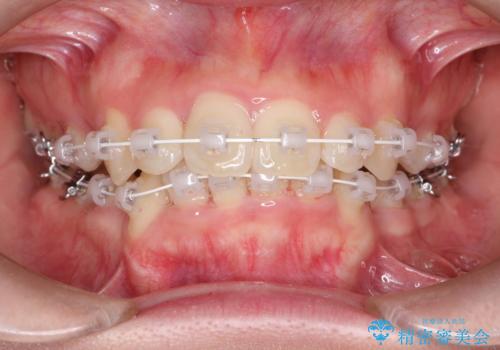

全体的ながたつき ワイヤーによる抜歯矯正で整った歯並びへ

- 上下の全体的ながたつきが気になるとのことで来院されました。

上下左右の前から4番目の歯を抜歯をして、ワイヤー矯正にて並べる計画としました。

患者様が装置を早期に除去したいという希望もあり、少々下の前歯のがたつきが残った状態で矯正を終了しました。

全体的ながたつきがなくなり、見た目の印象がよくなりました。